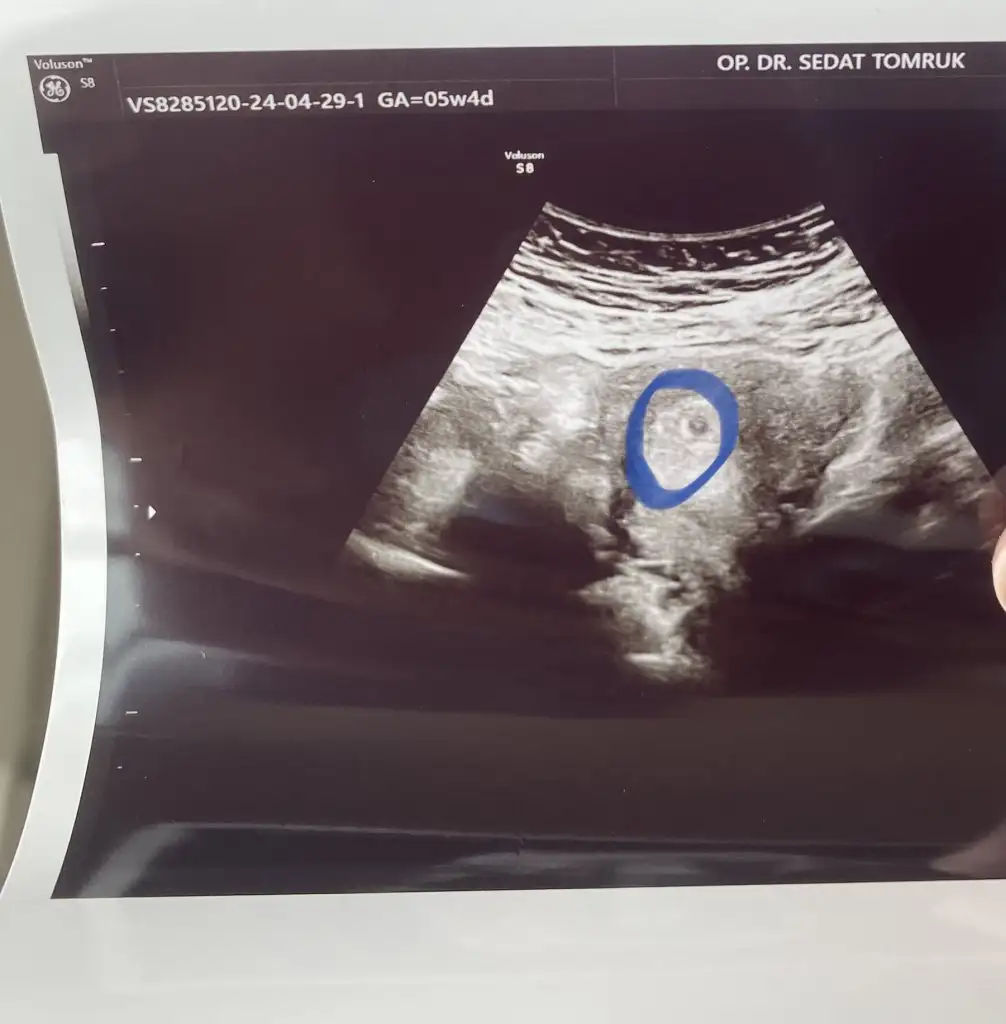

Canım iki kese var gibi ahahahaa ikiz mi yoksa

Nerde kız iki kese dkkfCanım iki kese var gibi ahahahaa ikiz mi yoksa

Bana da iki kese gibi geldi canım iki tane mercimek gördüm sankiNerde kız iki kese dkkf

Eşime söyledim de iki keseyse bu doktora gitmeyelim bi daha onu bile göremiyosa demişBana da iki kese gibi geldi canım iki tane mercimek gördüm sanki

Canım ben baktımda o kesenin olduğu bölümde tek kese var diğer gördükleri şey ise bence yumurtalıkların olduğu taraf olabilir yani doktor karında gezdiriyor sonuçta görmemesi imkansız olurduEşime söyledim de iki keseyse bu doktora gitmeyelim bi daha onu bile göremiyosa demişgördüm dediğiniz yeri ama orası ne ki acaba

Baksana sanki iki kese var gibi kendiminkini atcam bak şimdiEşime söyledim de iki keseyse bu doktora gitmeyelim bi daha onu bile göremiyosa demişgördüm dediğiniz yeri ama orası ne ki acaba

Evet yani çok uzak birbirlerinden çünkü o iki boşluk, başka bişi demek oCanım ben baktımda o kesenin olduğu bölümde tek kese var diğer gördükleri şey ise bence yumurtalıkların olduğu taraf olabilir yani doktor karında gezdiriyor sonuçta görmemesi imkansız olurdu

Bilemedim kuzum siz deyince başkalarının ultrasonlarına baktım da ikizlerin keseleri yan yana hep benimki biri anya biri konyada. Başka bişi herhalde oBu da benim ki canım

Bence ikiz gebelikte değerler çok yüksek çıkıyo siz kan testi yapmıştınız derlerdi yüksek diye benceBilemedim kuzum siz deyince başkalarının ultrasonlarına baktım da ikizlerin keseleri yan yana hep benimki biri anya biri konyada. Başka bişi herhalde o

280-910 çıkmıştı evet normal bence deBence ikiz gebelikte değerler çok yüksek çıkıyo siz kan testi yapmıştınız derlerdi yüksek diye bence